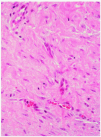

Se realizó estudio inmunohistoquímico, que mostró positividad para la actina muscular (fig. 6) y la vimentina, y negatividad para la desmina, actina a del músculo liso, citoqueratina, S-100, factor XIIIa y CD-34.

Fig. 6.--Tinción de inmunohistoquímica que muestra positividad para la actina muscular (x40).